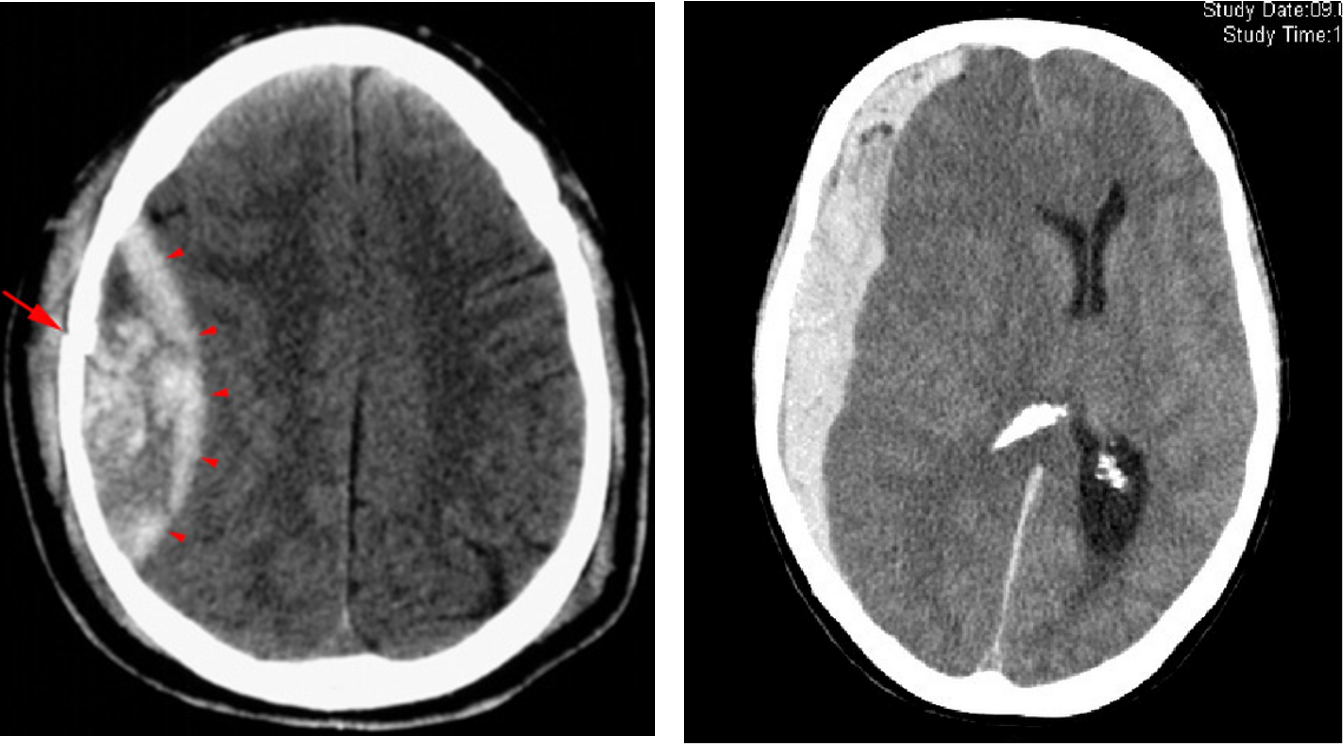

- Epidural or subdural hematoma: Treatment: evacuation

- Intracerebral hematoma & contusion

(Image: Epidural Hematoma & Subdural Hematoma)